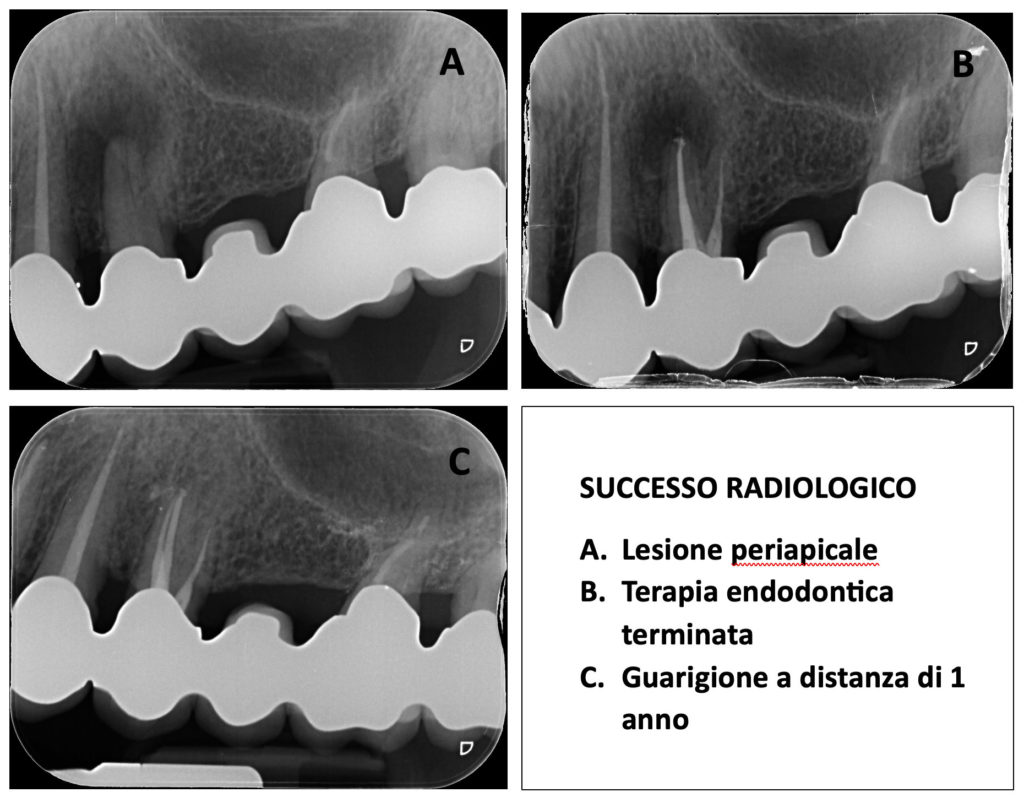

Distinguere i diversi gradi di successo clinico e radiologico

La valutazione della guarigione segue precisi criteri:

– Successo clinico: assenza postoperatoria di infezione e infiammazione (nessun dolore, assenza di dolorabilità alla palpazione e percussione, assenza di gonfiore e sinusite).

– Successo radiologico: a medio termine, la riduzione radiografica dell’area scura in 2D (rx endorale) o 3D (CBCT), fino a ritrovare il normale spazio del legamento parodontale.